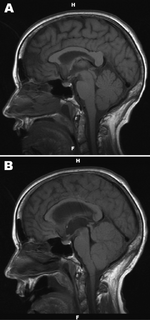

a,b) Noncontrast, sagittal T1-weighted magnetic resonance image of brain with suspected Powassan virus encephalitis